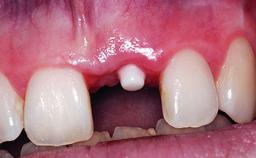

A 32-year-old female Caucasian patient with a compromised maxillary right central incisor was referred to us by a general dentist. Her chief complaints were discomfort and mobility of tooth 11 with unsatisfactory esthetics due to discoloration. The patient reported a previous trauma, some years earlier, as the origin of pathology on the afflicted tooth. Anamnesis was negative for any other dental or periodontal pathology in the remaining dentition. The patient did not take any medication and reported to be a light smoker (5–10 cigs/day). She had high esthetic expectations of her treatment. The extraoral examination revealed a high smile line with full exposure of her maxillary teeth and surrounding soft tissue in the area between the second premolars.

# of Implants 1

Type of Implants Reduced-Diameter|Two-Piece